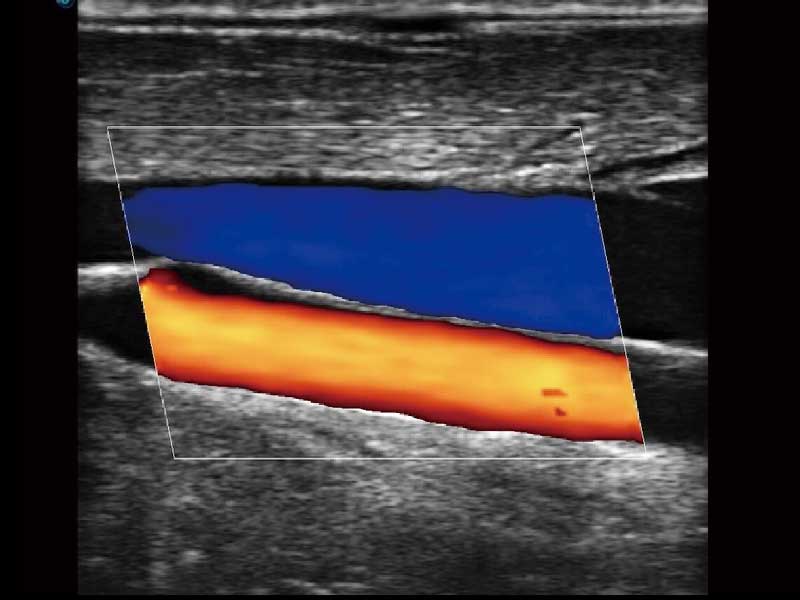

μ-Scan微米成像、空间复合成像、高分辨率血流成像。